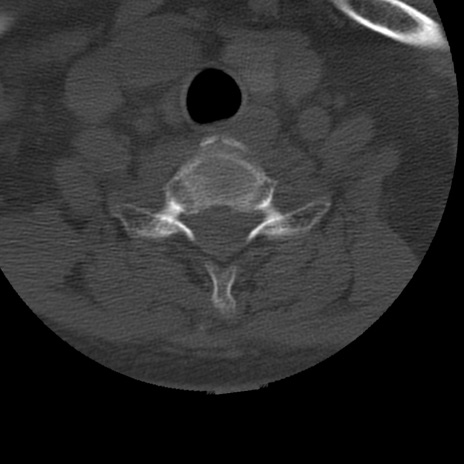

症例50 頚椎CT(横断像)

冠状断像

矢状断像